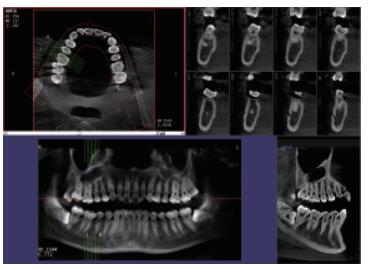

4、口腔CBCT(口腔CT)

CT相对其他牙片来讲,不管是功能还是设备上都是比较高级的,医生可在电脑上进行模拟种植360°的旋转查看口腔状况,不遗漏任何一个角落,主要用于根管治疗前、阻生牙、根尖囊肿、种植牙、正畸等。